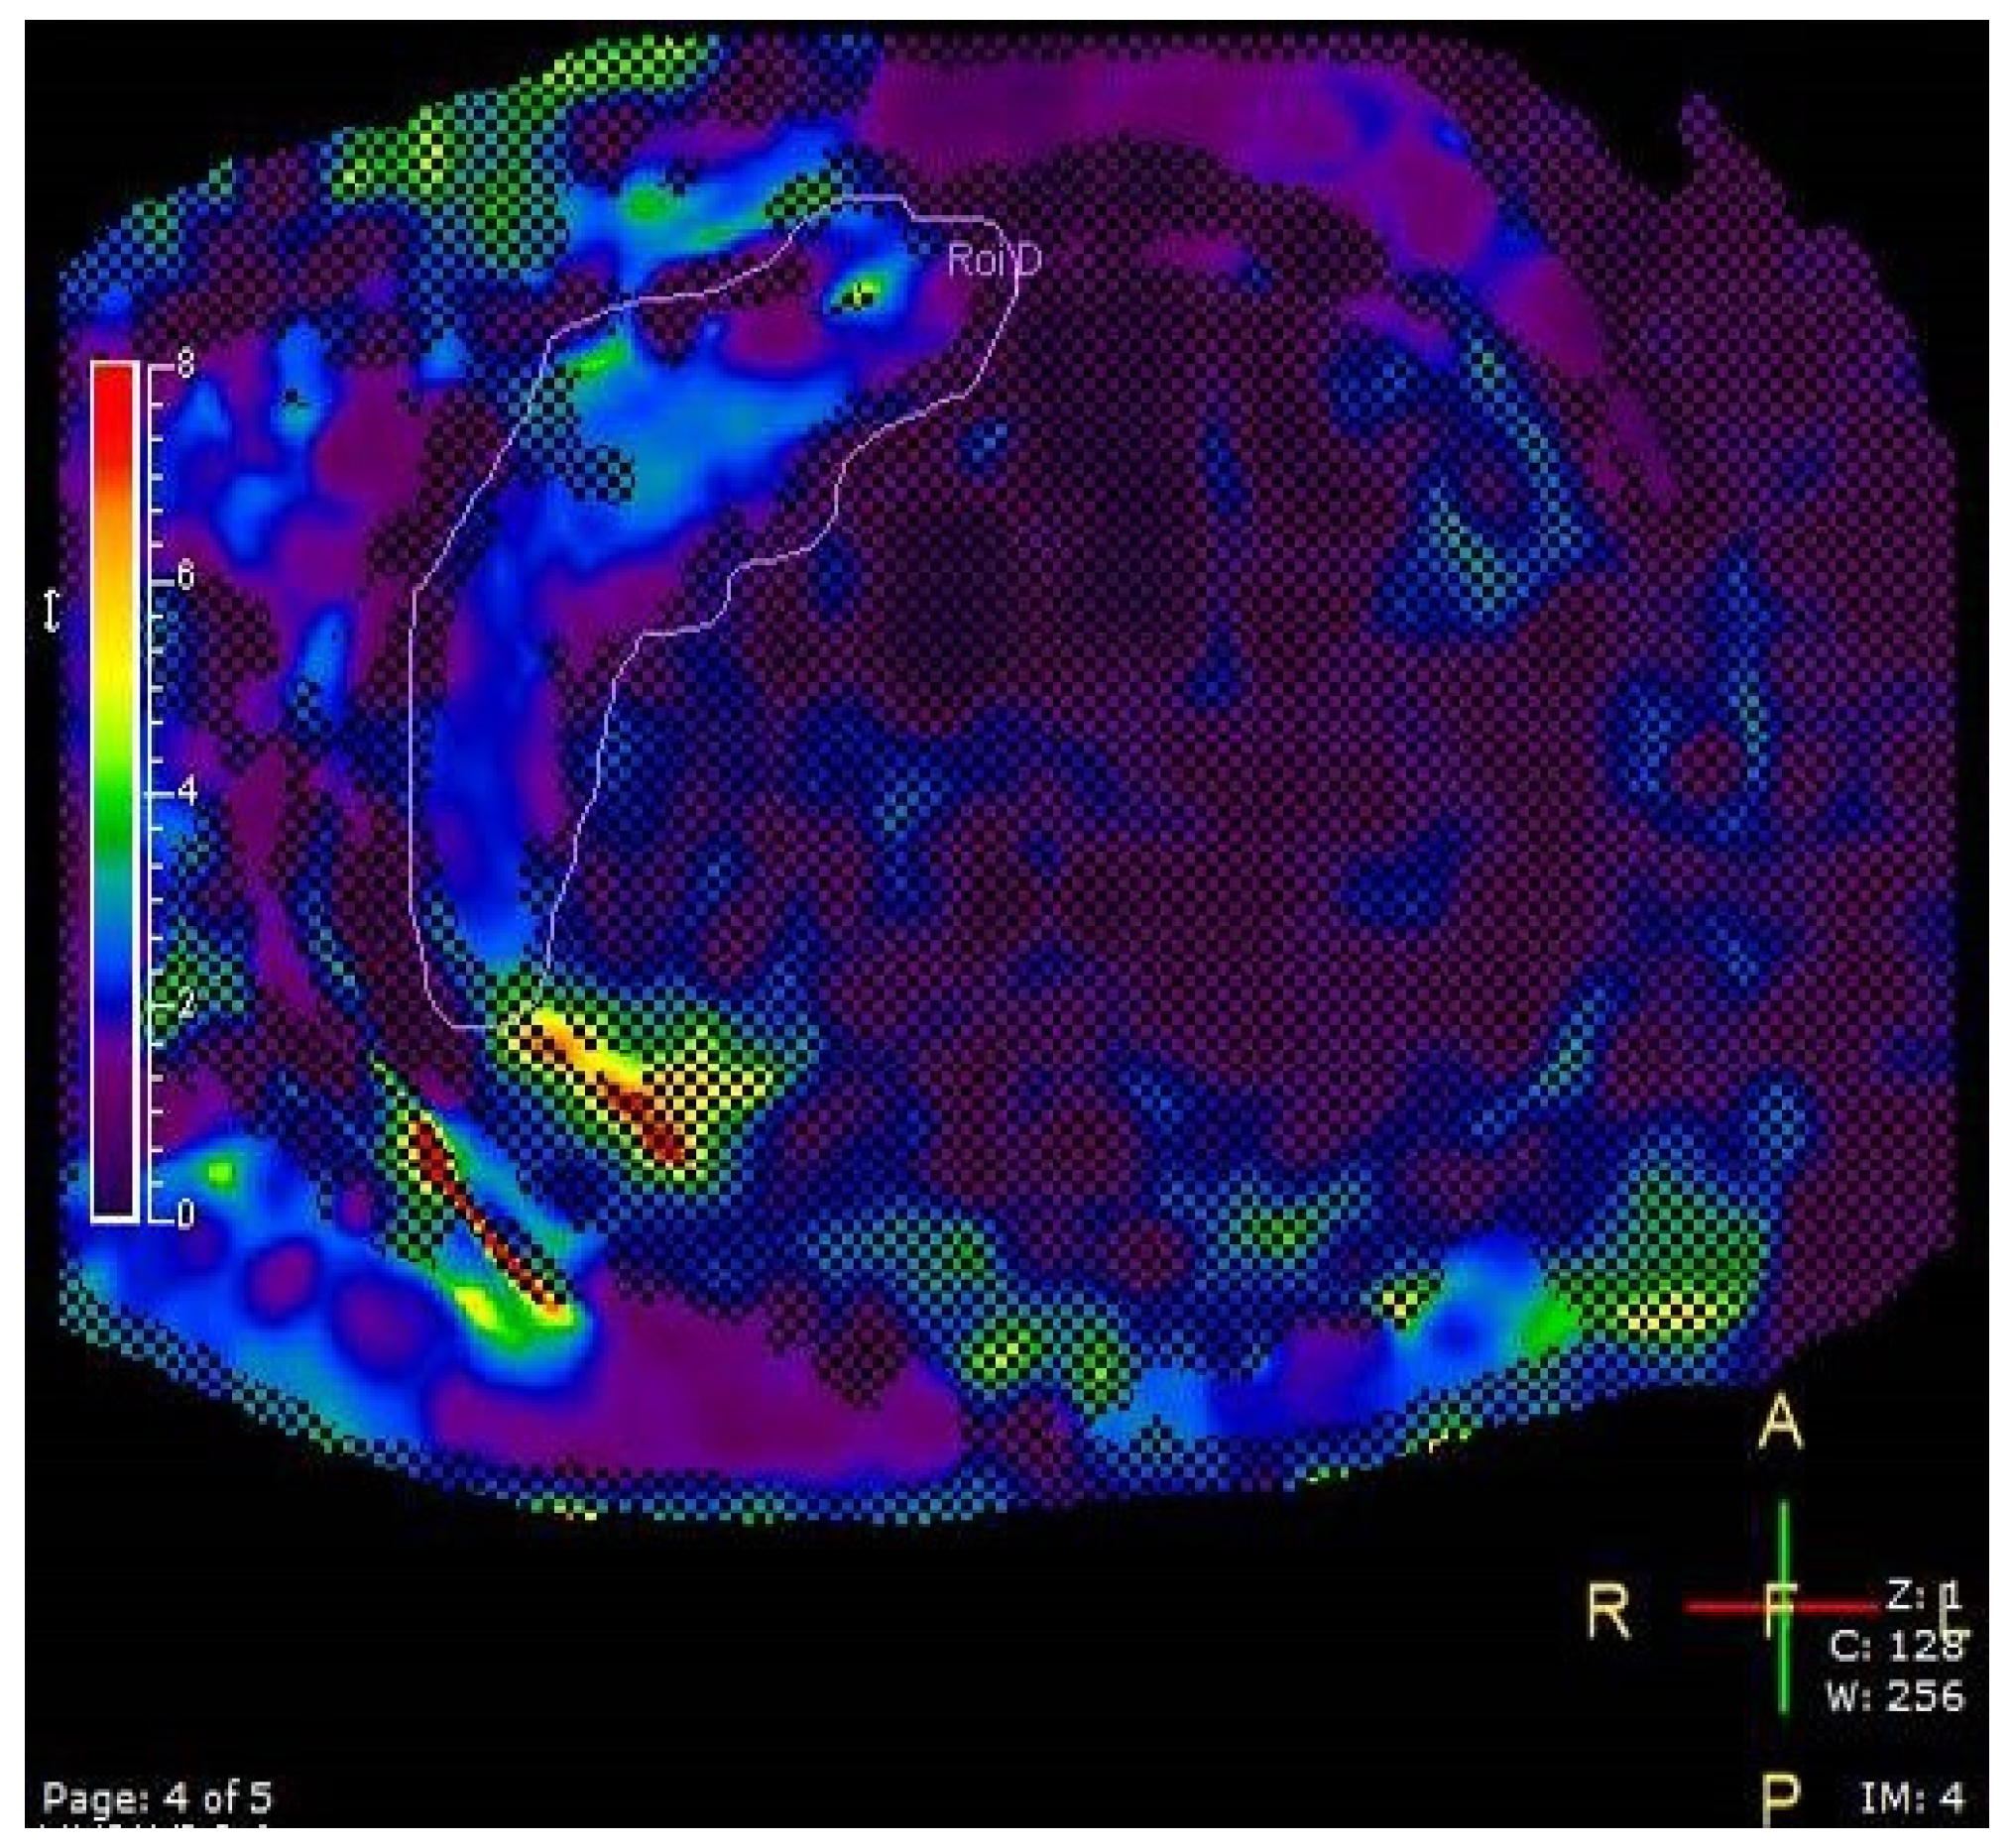

2.3.4. Liver Elastography